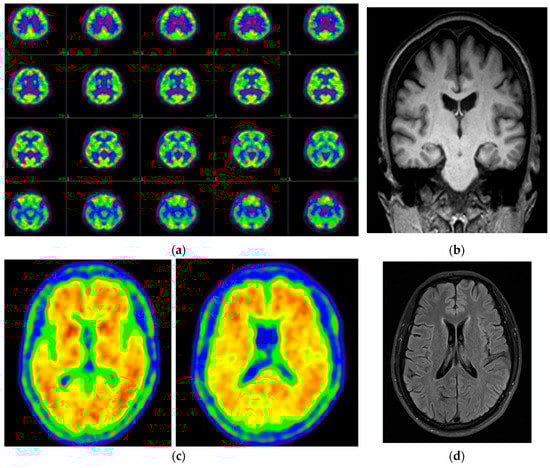

| Amyloid PET | Positive, frontal, parietal, precuneus/posterior cingulate, lateral temporal, and striatum | Diffuse amyloid retention in bilateral-parietal and temporal cortex | NA | Positive, posterior cingulate, and precuneus |

| FDG-PET | Mild bilateral hypometabolism in parietal lobe, precuneus, anterior cingulate, dorsal frontal lobe, and lateral temporal lobe with left predominance | NA | Bilateral hypometabolism in parietal and temporal cortices | NA |

| MRI | NA | Atrophy in frontal-temporal lobe, shrinkage of hippocampus | Global atrophy | No significant changes |